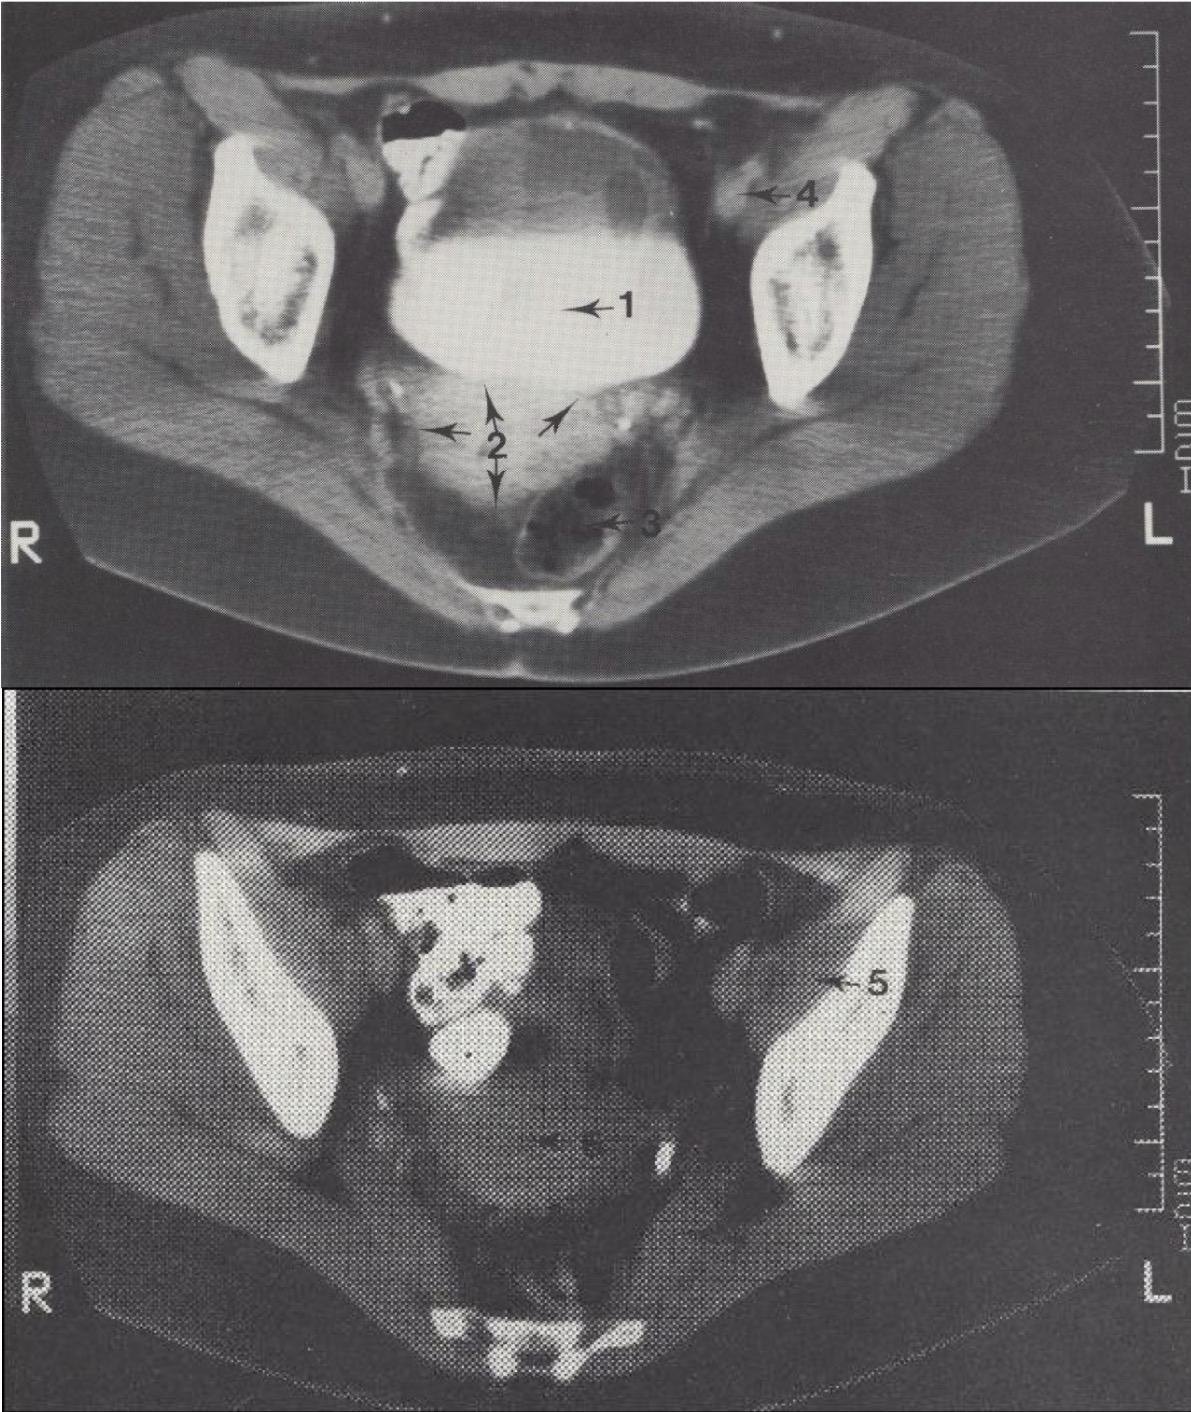

6

Fundus uteri (gimdos dugnas)

7

M. piriformis (kriaušinis raumuo)

Metodika

KT pjūviai atlikti virš acetabulum (gūžduobės). Naudotas intraveninis kontrastas (šlapimo takams) ir peroralinis kontrastas (žarnyno kilpoms).

Svarbu

Pacientei gulint, šlapimo pūslėje matomas kontrasto išsisluoksniavimas: sunkesnis jodo kontrastas nusėda apačioje, o lengvesnis šlapimas – viršuje.

Topografija

Gimdos šešėlis (corpus uteri) matomas tarp tiesiosios žarnos (rectum) ir šlapimo pūslės (vesica urinaria).